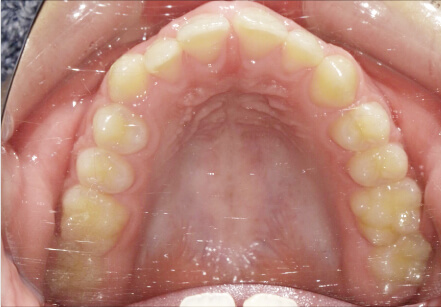

叢生の症例

41歳

/

女性

相談内容

横から見た時のガタガタが気になる

カウンセリング・診断結果

インビザライン、正中は上11に合わせていく、抜歯・拡大装置・IPR・アタッチメントOK

治療内容・方法

アライナー矯正

術後の経過・現在の様子

クリアライナー使用

治療のリスク

痛み・歯根吸収・歯肉退縮・虫歯・後戻り

費用・治療期間

880,000円、7ヶ月

トレーニングなど